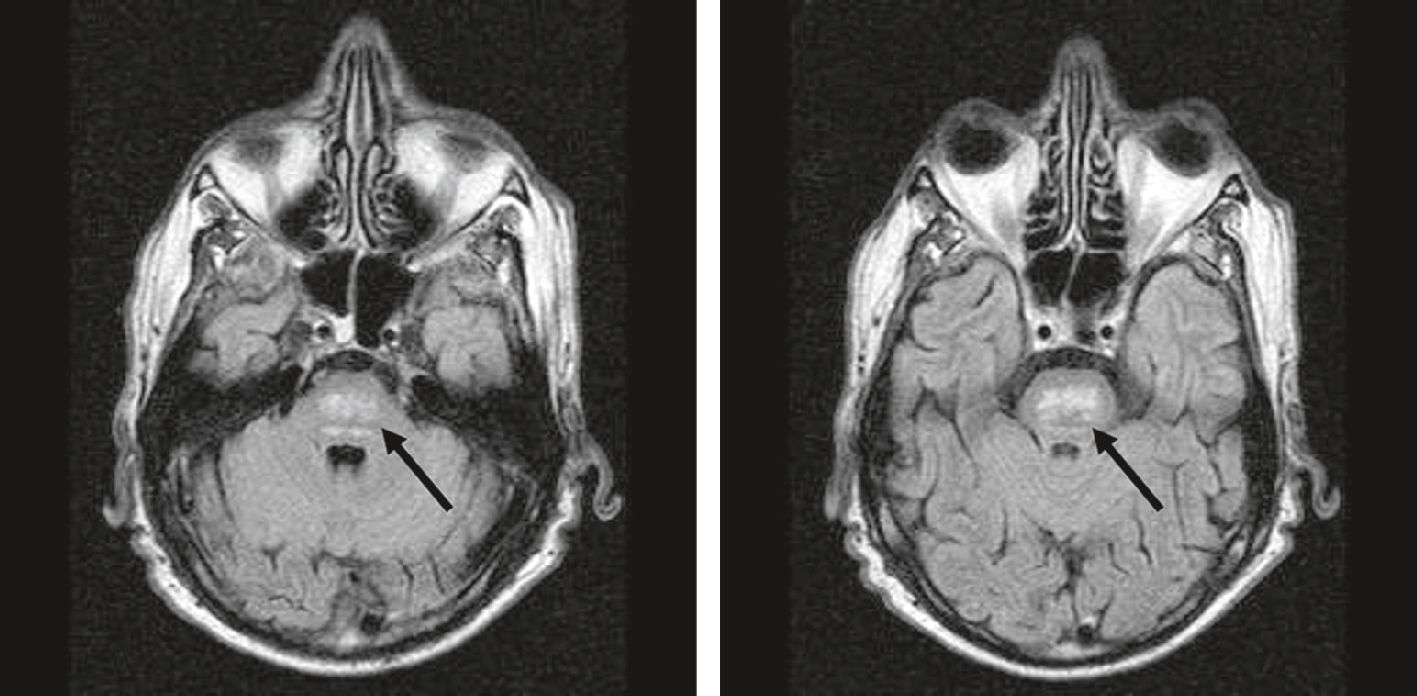

Rare, de physiopathologie complexe, associée à la dénutrition, la myélinolyse centropontine est favorisée par l’hyponatrémie et sa correction trop rapide. Elle comporte un trouble de la vigilance avec une tétraplégie et des signes pseudobulbaires traduisant la démyélinisation des fibres du centre du pont (ou protubérance) visible à l’IRM cérébrale (fig. 2.3 : hypersignal T2 et FLAIR), parfois étendue à la substance blanche hémisphérique. Le pronostic est péjoratif. Le traitement est préventif : correction progressive des hyponatrémies profondes.

Myélinolyse centropontine. IRM axiale FLAIR. Hypersignaux du pont (ou protubérance) (flèches noires).

Sur ces deux coupes axiales pondérées T1, on observe au centre du pont une lésion bien circonscrite, clairement désignée par une flèche noire sur chaque image. À gauche, l’IRM montre une zone d’hyposignal, homogène, centrée dans la partie centrale du pont, sans effet de masse ni œdème périphérique. À droite, l’image met en évidence une région hyperintense anormale en T2, également localisée dans le pont. L’aspect est typique d’une atteinte de la substance blanche centrale du tronc cérébral, en accord avec une myélinolyse centropontine. Les structures environnantes telles que les pédoncules cérébelleux et les noyaux de la base semblent épargnées. Ce tableau radiologique est évocateur d’une démyélinisation osmotique, souvent liée à une correction trop rapide d’une hyponatrémie sévère.